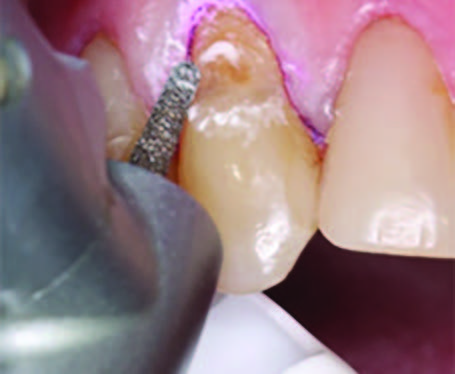

To improve isolation and soft tissue access, a retraction cord was placed before initiating the procedure (Fig. 2). The tooth was evaluated using a caries indicator dye (Kuraray Noritake Dental), helping to identify any remaining infected tissue beneath the dislodged composite (Fig. 3). Decay removal was completed with a diamond bur, and the enamel was bevelled using a starburst pattern to enhance aesthetic blending (Fig. 4). This preparation design was chosen for visual integration rather than bond strength enhancement.

Figure 4. Preparation of the lesion is completed with diamond bur and starburst beveling pattern to enhance aesthetic blending.